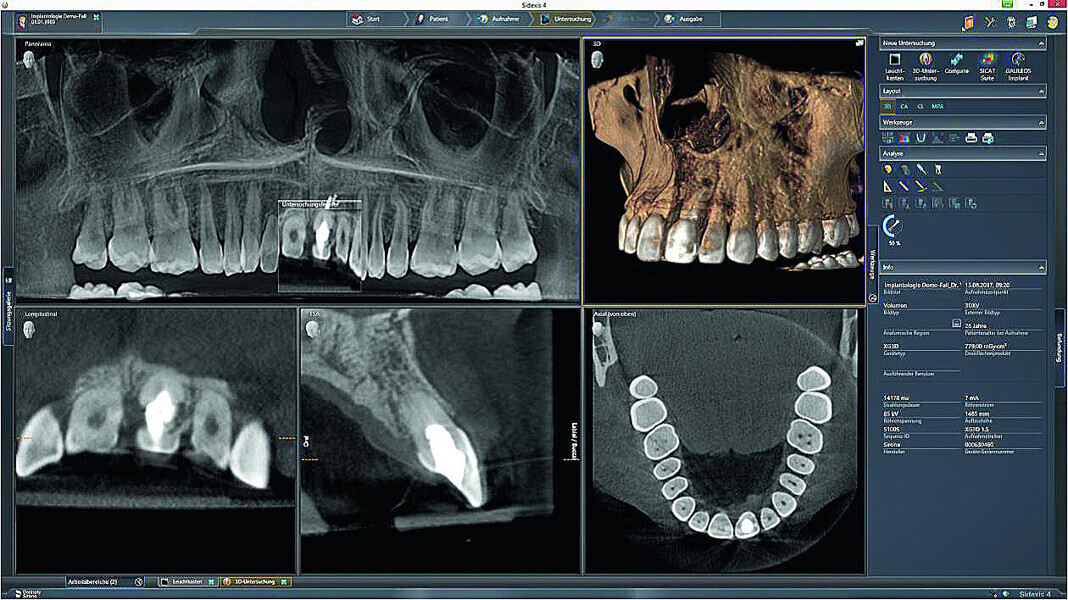

Fig. 3: The initial situation in 3-D in the Sidexis 4

imaging software (Dentsply Sirona) showed good apical bone substance with the possibility of immediate implantation.